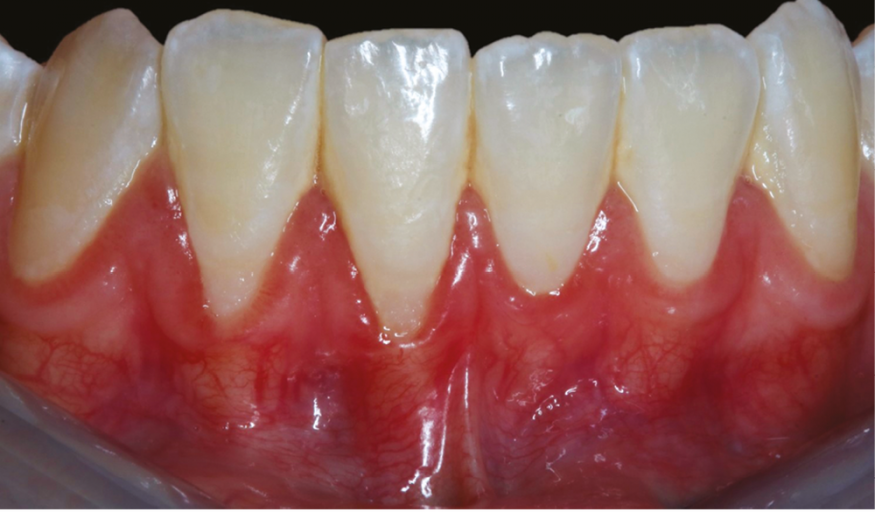

– les signes cliniques de l’inflammation gingivale : érythème/rougeur, œdème, douleur (parfois une simple gêne ou démangeaison), chaleur et perte réversible de fonction de l’épithélium jonctionnel (qui joue le rôle de barrière entre le milieu intérieur et le milieu extérieur). À cela s’ajoute de manière inconstante une altération du festonnage gingival (fig. 1) ;

1. Gingivite liée à la plaque sur parodonte réduit chez une patiente de 23 ans sans antécédent de parodontite. La gencive est rouge vernissée, œdématiée et la présence de plaque dentaire et de tartre en quantité importante est objectivée à l’œil nu. Le festonnage gingival est altéré sur toutes les papilles du bloc incisivo-canin mandibulaire.